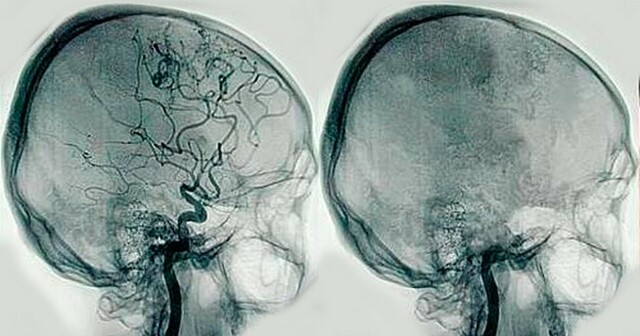

• Angiografía

Angiografía

Egas Moniz realiza la primera angiografía ( examen de los vasos sanguíneos que utiliza imágenes por rayos X y una inyección de un material de contraste radiopaco para obtener imágenes de las arterias del cerebro, corazón, riñones, tracto gastrointestinal, aorta, cuello, pecho, extremidades y del sistema circulatorio).